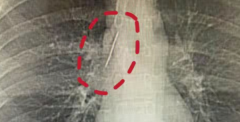

• 17岁小伙征兵体检发现肺上有根针,十几年都没事真是奇迹

医生 大血管 小陆 2026/04/02